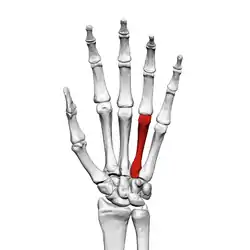

![]() Fourth metacarpal of the left hand (shown in red). Palmar view. | |

The base is small and quadrilateral; its superior surface presents two facets, a large one medially for articulation with the hamate, and a small one laterally for the capitate.

On the radial side are two oval facets, for articulation with the third metacarpal; and on the ulnar side a single concave facet, for the fifth metacarpal.